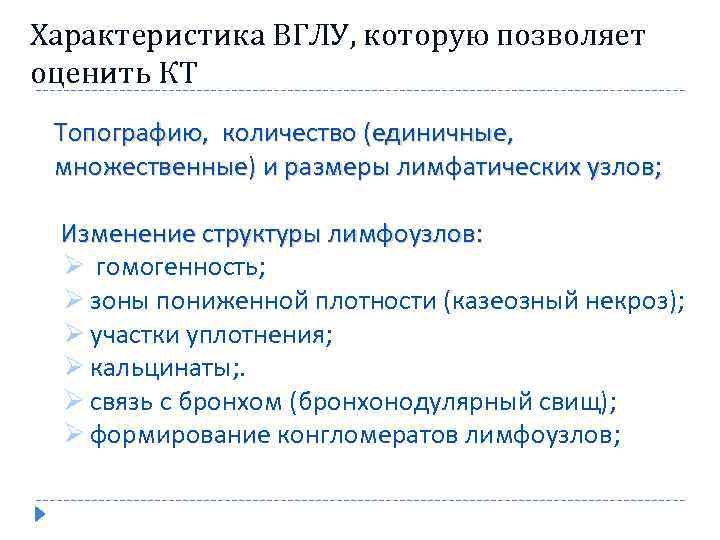

Характеристика ВГЛУ, которую позволяет оценить КТ Топографию, количество (единичные, множественные) и размеры лимфатических узлов; Изменение структуры лимфоузлов: Ø гомогенность; Ø зоны пониженной плотности (казеозный некроз); Ø участки уплотнения; Ø кальцинаты; . Ø связь с бронхом (бронхонодулярный свищ); Ø формирование конгломератов лимфоузлов;

Характеристика ВГЛУ, которую позволяет оценить КТ Топографию, количество (единичные, множественные) и размеры лимфатических узлов; Изменение структуры лимфоузлов: Ø гомогенность; Ø зоны пониженной плотности (казеозный некроз); Ø участки уплотнения; Ø кальцинаты; . Ø связь с бронхом (бронхонодулярный свищ); Ø формирование конгломератов лимфоузлов;

Характеристика ВГЛУ, которую позволяет оценить КТ (слайд № 2) Состояние перинодальной и медиастинальной клетчатки средостения: Ø плевромедиастинальные спайки; Ø уплотнение клетчатки средостения; Состояние аксильного интерстиция: Ø нечеткость, размытость его контуров; Ø деформация, утолщение и сближение прикорневых сосудов и бронхов, наличие перибронхиальных муфт; 42

Характеристика ВГЛУ, которую позволяет оценить КТ (слайд № 2) Состояние перинодальной и медиастинальной клетчатки средостения: Ø плевромедиастинальные спайки; Ø уплотнение клетчатки средостения; Состояние аксильного интерстиция: Ø нечеткость, размытость его контуров; Ø деформация, утолщение и сближение прикорневых сосудов и бронхов, наличие перибронхиальных муфт; 42